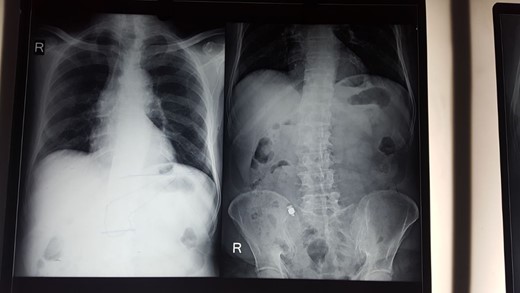

Retained video capsule removed (Fig. 3) and stricturoplasty done extracorporeally by taking out the loop through an incision in right iliac region. Patient discharged on Day 7 with liquid diets. Post-operative picture of patient (Fig. 4).